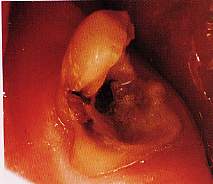

Figg.

20-21 Lesione di 3° gardo della biforcazione del 4.7 cui si associa

una lesione endoparodontale. |

Nel

caso illustrato nelle figure 20-23 dopo lo scollamento del lembo

mucoperiosteo e la separazione delle radici, si è proceduto alla

terapia del vasto cratere interadicolare con osso eterologo di Kiel.